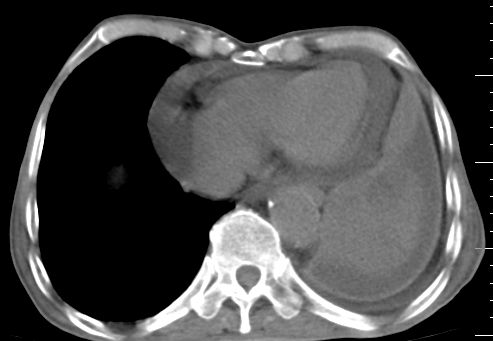

标题: CT10141:男、84岁,咳嗽、咯血1年。 [打印本页]

标题: CT10141:男、84岁,咳嗽、咯血1年。

左侧中心型肺癌,左侧胸腔积液部分包裹,心包积液,肿膈淋巴结显示。

左下中央型肺癌伴阻塞性不张,肺炎,左侧包裹性胸腔积液\\心包积液

左肺中心性肺癌并肺不张,同侧 胸膜及心包转移,左肺癌性淋巴管炎